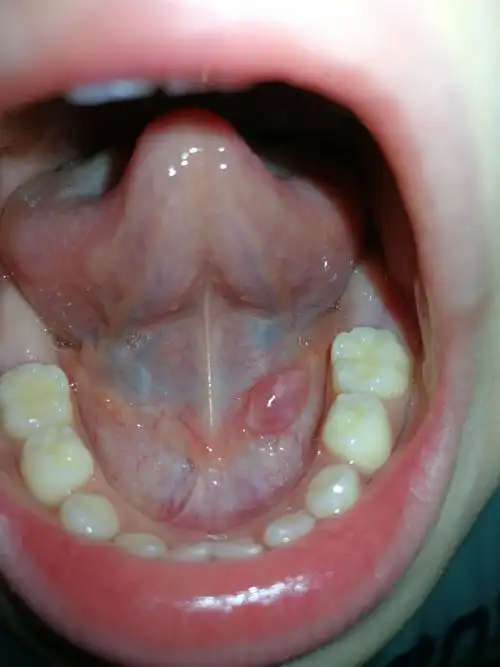

老高老高了的皮肤科#高主任口腔舌头下面,正常吗? #帮她问问大家